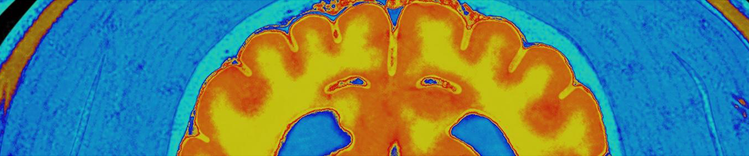

NEURONENMASSE UND HIRN-MRT

Veränderungen im alternden Gehirn

Zu den physischen Veränderungen des Gehirns, die mit dem Altern einhergehen, gehören:

- Atrophie (Schrumpfung) des Gewebes in einigen Regionen

- erhöhtes Ventrikelvolumen

- Verlust von Neuronen und Synapsen und verminderte Bildung neuer Neuronen

- Anhäufung von abnormen Proteinen

Weitere signifikante Veränderungen sind:

- Reduzierte Glukoseverwertung

- Chronische Entzündungen

- Vaskuläre Veränderungen

- Verminderung/Verschlechterung der Myelinisierung

- Anomalien von Astrozyten und neuronenunterstützenden Zellen

- Beeinträchtigte Zerstörung und Beseitigung von abnormalen/geschädigten Proteinen

- Veränderungen der Genexpression